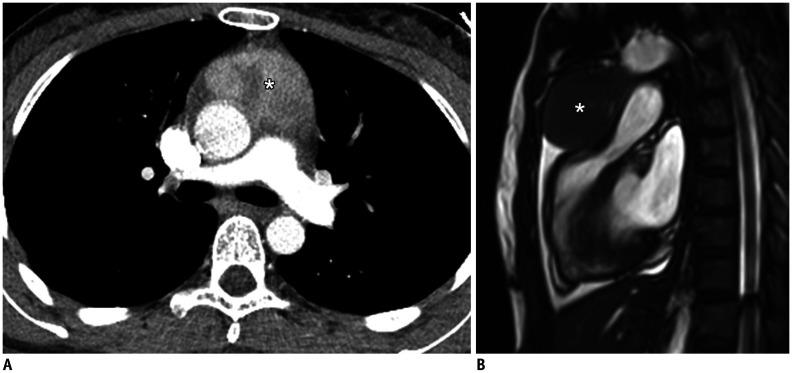

Magnetic resonance imaging (MRI) has become a crucial tool for evaluating mediastinal masses considering that several lesions that appear indeterminate on computed tomography and radiography can be differentiated on MRI. Using a three-compartment model to localize the mass and employing a basic knowledge of MRI, radiologists can easily diagnose mediastinal masses. Here, we review the use of MRI in evaluating mediastinal masses and present the images of various mediastinal masses categorized using the International Thymic Malignancy Interest Group's three-compartment classification system. These masses include thymic hyperplasia, thymic cyst, pericardial cyst, thymoma, mediastinal hemangioma, lymphoma, mature teratoma, bronchogenic cyst, esophageal duplication cyst, mediastinal thyroid carcinoma originating from ectopic thyroid tissue, mediastinal liposarcoma, mediastinal pancreatic pseudocyst, neurogenic tumor, meningocele, and plasmacytoma.

磁共振成像(MRI)已成为评估纵隔肿块的重要工具,因为 CT 和 X 线摄影上表现为不确定的一些病变可以在 MRI 上区分。使用三室模型定位肿块并运用 MRI 的基本知识,放射科医生可以轻松诊断纵隔肿块。在这里,我们回顾了 MRI 在评估纵隔肿块中的应用,并展示了使用国际胸内恶性肿瘤兴趣小组的三室分类系统对各种纵隔肿块进行分类的图像。这些肿块包括胸腺增生、胸腺囊肿、心包囊肿、胸腺瘤、纵隔血管瘤、淋巴瘤、成熟畸胎瘤、支气管囊肿、食管重复囊肿、起源于异位甲状腺组织的纵隔甲状腺癌、纵隔脂肪肉瘤、纵隔胰腺假性囊肿、神经源性肿瘤、脑脊膜膨出和浆细胞瘤。